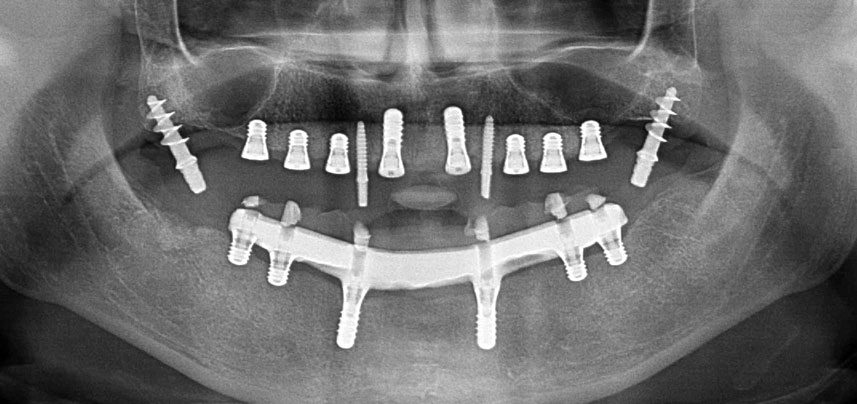

Post-operative panoramic radiograph

Fig. 10: The post-operative panoramic radiograph shows all implants in appropriate positions, including the pterygoid provisional implants.